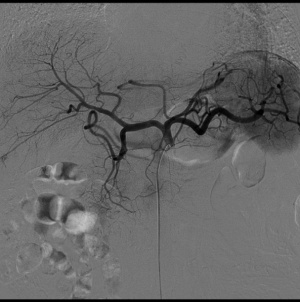

脳血管検査

脳出血の原因となる動脈瘤(こぶ)や脳血管の奇形などの手術の前に、その状態を詳しく観察する際に行います。また、血管が細くなったり詰まったりしたのを調べるうえでも欠かせない検査です。脳腫瘍の手術の前には、腫瘍の近くを重要な血管が通っていないか、また、腫瘍を栄養している血管などを調べます。

![]() |